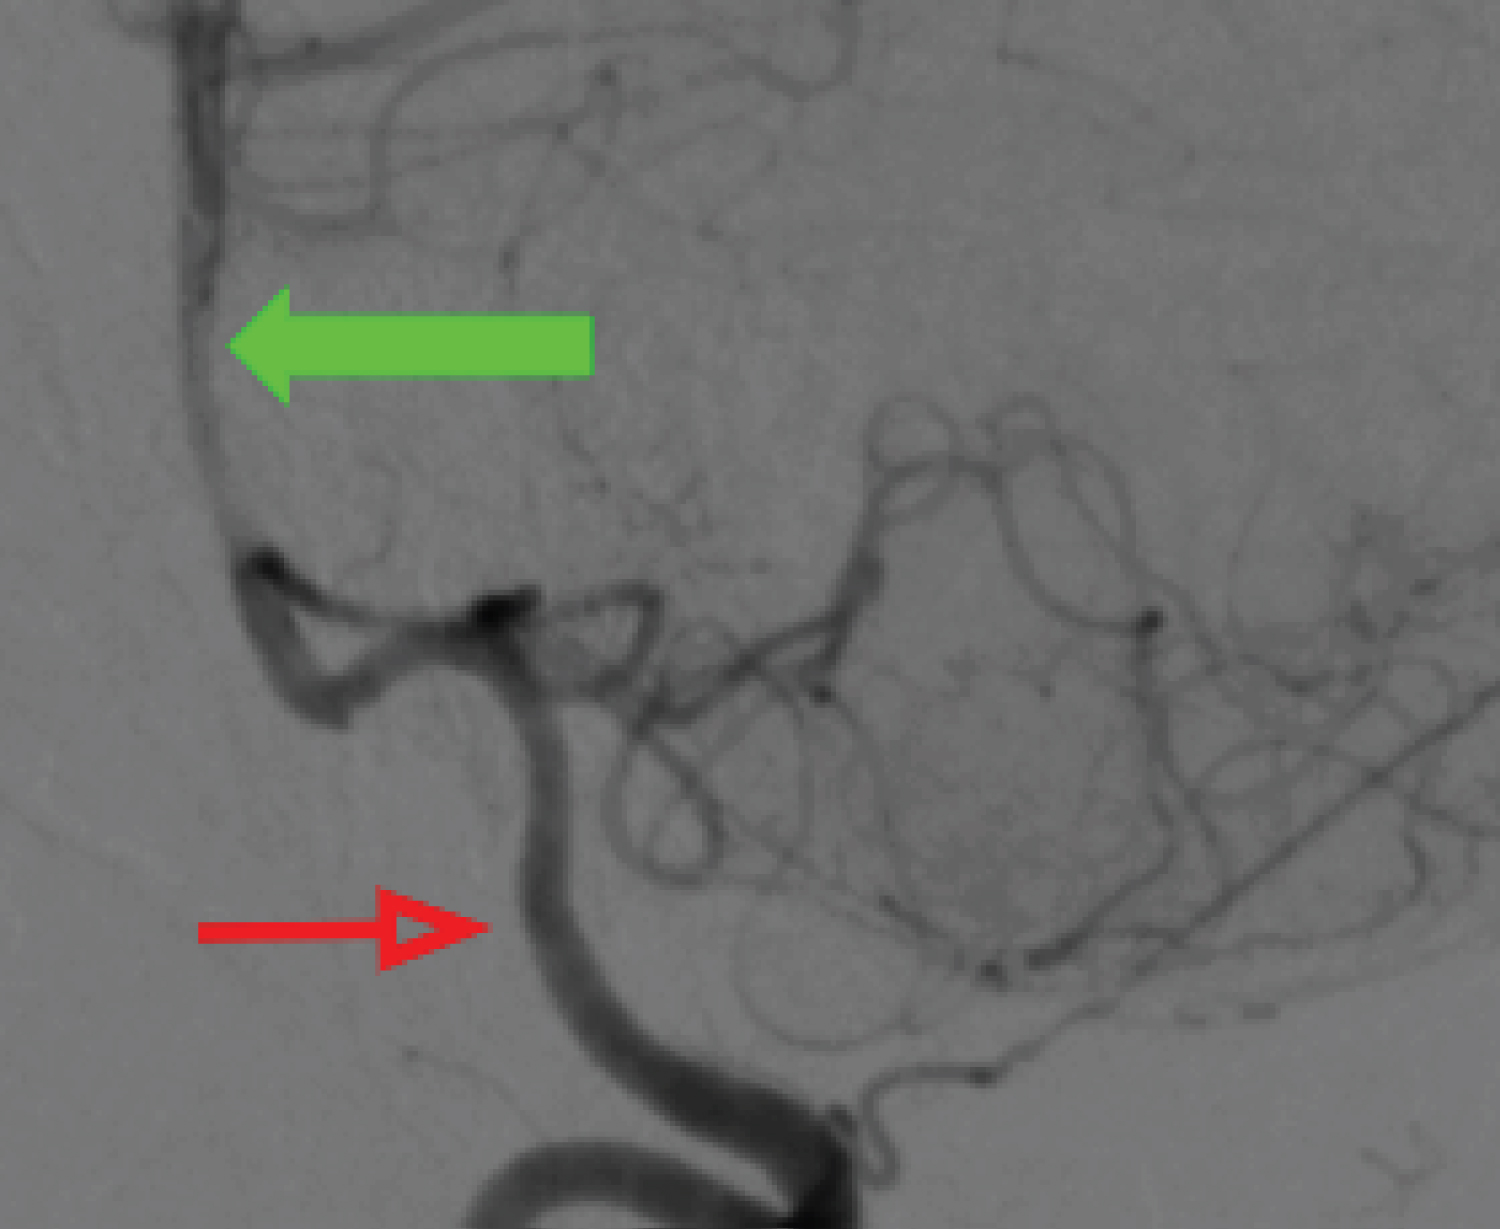

A.L.L.S., woman, 53-years-old, with a history of headache and previous clipping of an unruptured cerebral aneurysm of the Anterior Communicating Artery (AcoA) in 2018. During follow-up, she underwent Magnetic Resonance Angiography (MRA) 3D-TOF of cerebral vessels, which demonstrated a saccular aneurysm in the cavernous segment of the right Internal Carotid Artery (ICA), measuring 5.9 mm in its largest diameter and with a neck of 4.8 mm (Figure 1). This lesion is associated with the presence of a Persistent Primitive Trigeminal Artery on the right (PPTA), which arises immediately proximal to the aneurysm (aneurysm orientation).

Figure 1: Arterial 3D-TOF cerebral MRA - white curved arrow pointing to saccular aneurysm, green arrow indicating persistent trigeminal artery, red arrow indicating right internal carotid artery. View Figure 1

The diagnostic workup was extended with cerebral arteriography, during which the trident sign (Figure 2) compatible with Persistent Trigeminal Artery was observed, along with the absence of the right posterior communicating artery (P-com), classifying the Persistent Primitive Trigeminal Artery as type I of Saltzman. The left P-com originates from fetal circulation (Figure 3), while the right vertebral artery terminates in the right Posterior Inferior Cerebellar Artery (PICA), and the left vertebral artery is dominant (Figure 4).

Figure 4: Dominant left vertebral arteriography in profile, arterial phase (red arrow), filling the basilar artery (green arrow). View Figure 4